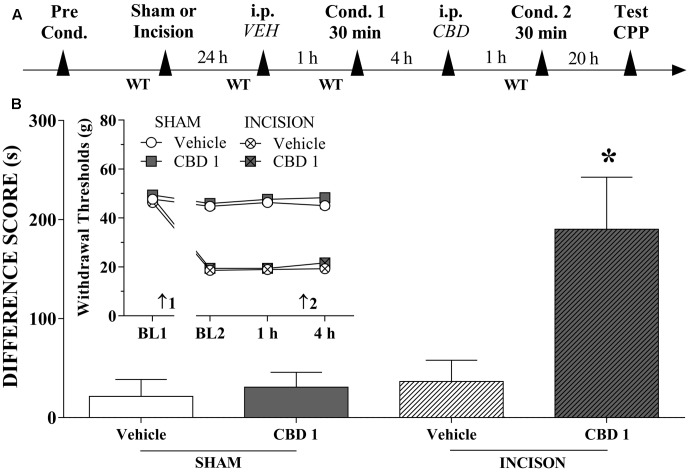

Systemic CBD Induces CPP

We investigated whether systemically administered CBD could selectively activate reward circuits in injured rats. A timeline of the protocol for the experiments is shown in Figure 3A. CBD (1 mg/kg) induced significant CPP in injured rats [F(3,42) = 6.2; p < 0.01]. CBD (0.5 mg/kg) induced no significant CPP in injured rats (not shown in Figures). CBD (1 mg/kg) did not induce CPP in sham rats (Figure 3B). One-way ANOVA with Tukey’s post hoc test demonstrated a significant effect of CBD (1 mg/kg) compared with all other groups (p < 0.05). Intraperitoneal administration of CBD (1 mg/kg) had no effect on paw WTs (insert in Figure 3B). There was a significant effect of time [F(3,126) = 254.3; p < 0.01], treatment [F(1,42) = 6.01; p < 0.01] and condition [F(1,42) = 929.0; p < 0.01] but there was no interaction between three factors. These results suggest that CBD (1 mg/kg), which is not rewarding in sham-operated rats, become rewarding in injured rats, presumably because of pain relief.